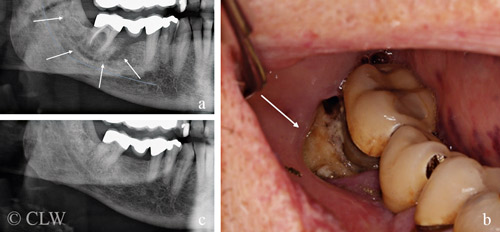

Figur 2. 78-årig man med prostatacancer och spridning till skelettet har fått behandling med denosumabinjektioner under ca 2 års tid. a) Panoramaöversikt visar en ca 3–4 cm stor sekvester runt en kindtand som är stödtand i en bro. b) Kliniskt ses en ca centimeterstor benblotta intill kindtanden. c) Ett år tidigare har röntgenutredningen inte kunnat fastställa någon patologi i området, dock beskriver patienten periodvis värk från området.